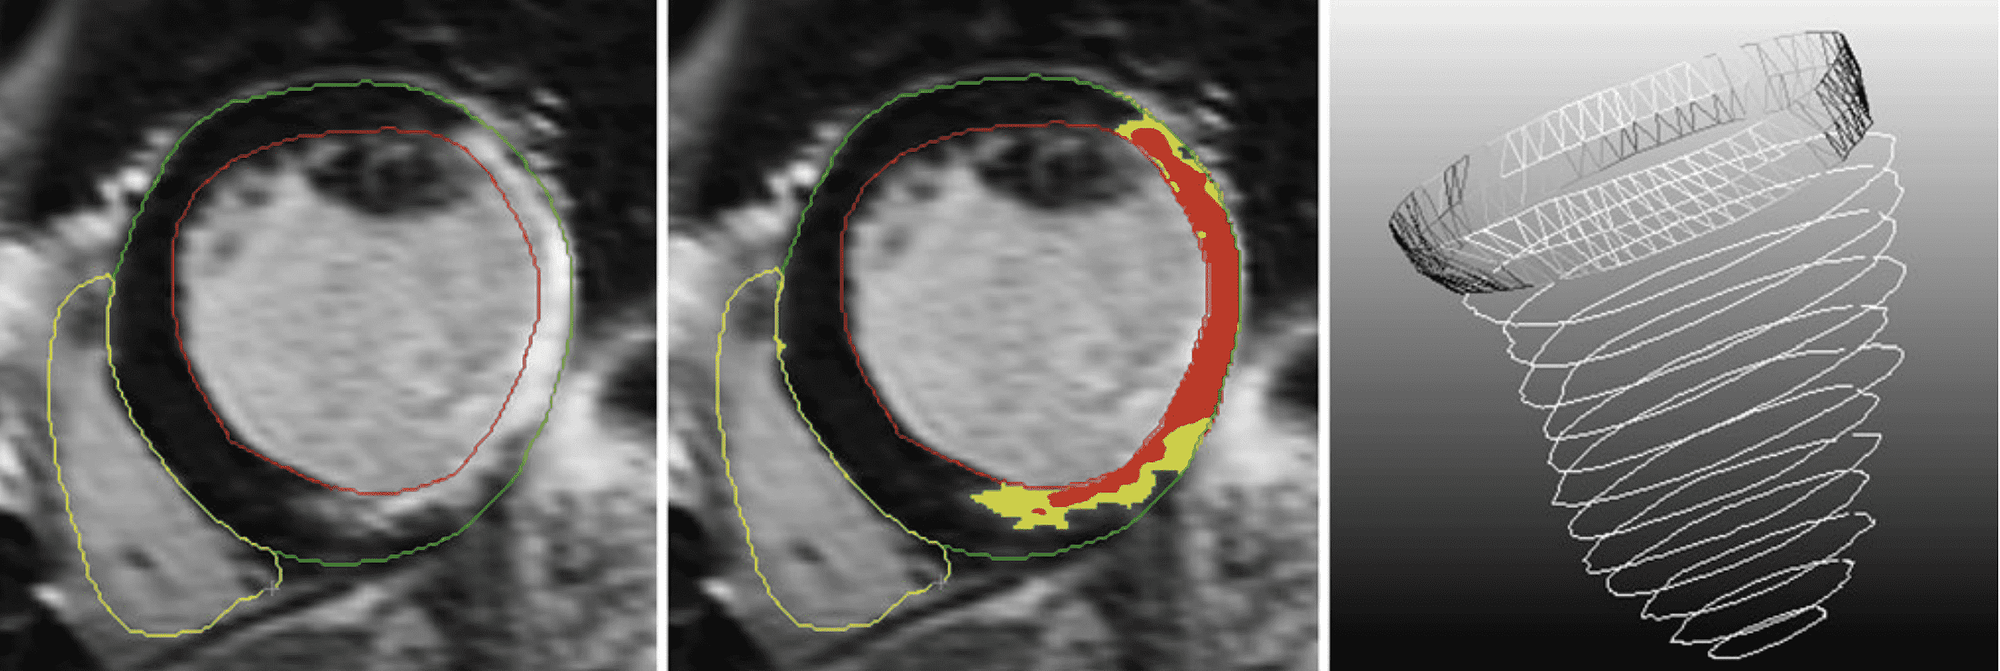

The preprocessing steps. Left Definition of the contours, Middle Definition of scar (gray zone (in yellow) and core zone (in red)) and Right The composition of the mesh based on the contours in 3D. The last described preprocessing step of indicating the position of the origin of the left main coronary artery is not included in this figure